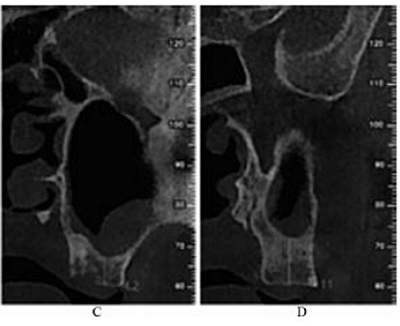

CBCT示:上頜竇內見液平面約達竇腔1/3(考慮為沖洗液未吸干凈),上頜竇垂直高度得到補足,26牙高度8.4mm,27牙高度為9.5mm(圖3)。患者拒絕穿刺液送病理檢查。

圖3 上頜竇外提升術后CBCT。

注:A,矢狀面;B,26頰舌向切面;C,27頰舌向切面;D,28頰舌向切面。